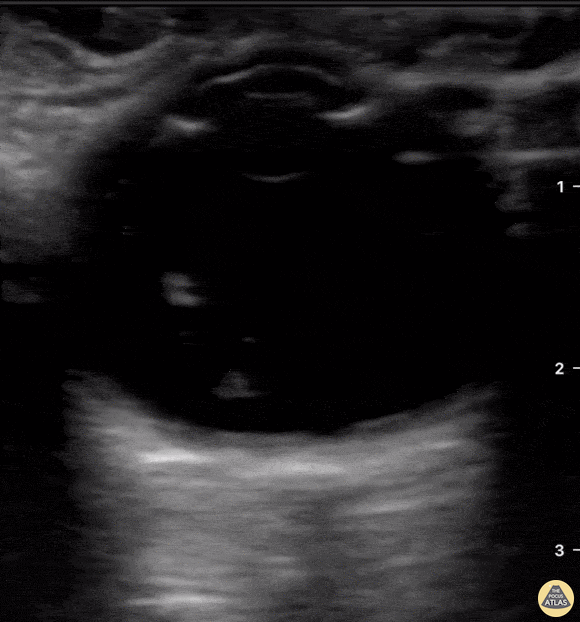

Orbital - Endogenous Endophthalmitis

A middle aged female with ESRD and longstanding percutaneous HD catheter with recent MSSA bacteremia was admitted with septic shock. She subsequently developed subacute bilateral visual loss (OS > OD). Clinical suspicion of endogenous endophthalmitis was initially supported by POCUS notable for heterogenous intraoccular material within vitreous. She was immediately started in intravitreal antibiotics in addition to previously initiated systemic antibiotics. Diagnosis of endogenous endophthalmitis was subsequently confirmed by vitrectomy. Tessa W. Damm, DO Intensivist, Critical Care Medicine & Neurocritical Care. Wisconsin, USA. @DrDamm